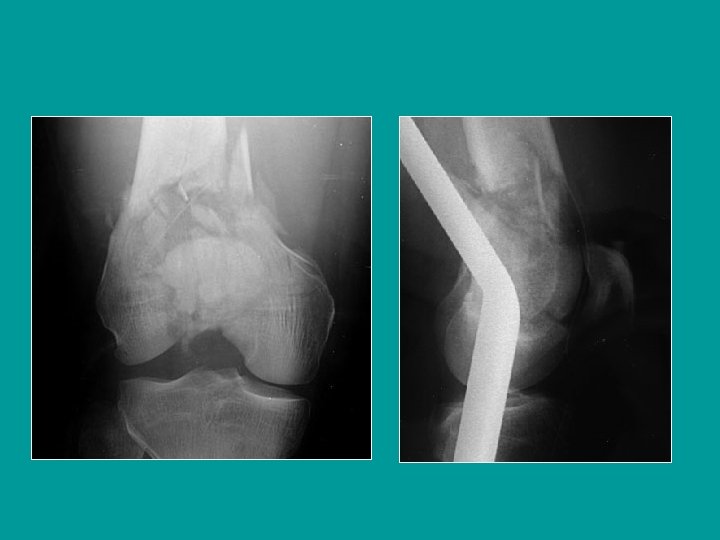

Desplazamiento de las fracturas supracondíleas Basculación posterior y distal del fragmento distal (gemelos). Protrusión anterior del fragmento proximal que empuja al cuádriceps

Fractura supra e inter-condílea Fractura articular conminutiva

Reducción por tracción trans-tibial

La corrección de la basculación requiere una tracción fuerte y un apoyo posterior